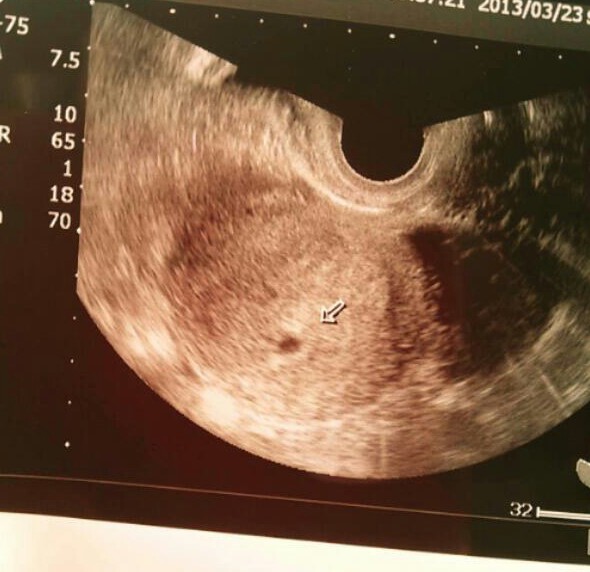

エコー写真はこちら。

黒豆みたい。